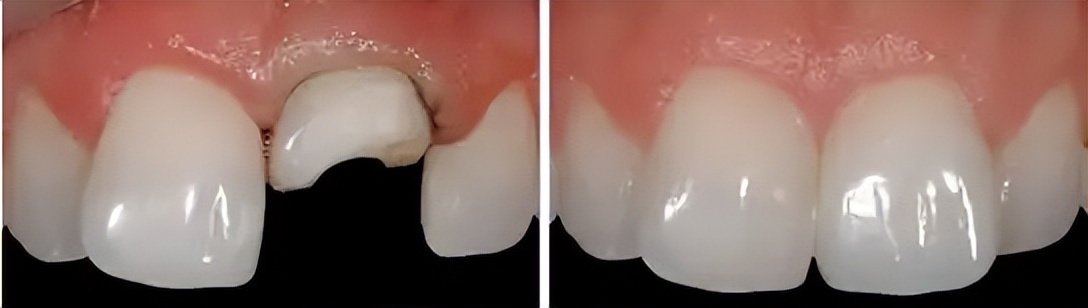

如果前牙外伤,单纯的牙冠缺损,牙根没有问题,大致情况如下图

1.树脂修复(价格200到1000左右)

这种情况,缺损小的,可以直接用光固化树脂修复换牙,用光固化树脂的优点是就诊时间短,基本不磨牙齿,费用相对比较低(一般3m树脂价格200到1000不等,如果是美塑树脂,价格更高一些,一分钱一分货)

2.全瓷贴面(价格2000到5000不等)。

牙齿缺损,变色,散在间隙,都是瓷贴面的适应证,以前树脂没有发展起来之前,基本都是贴面修复,贴面颜色更好,更持久。现在随着粘接技术的提高,美塑树脂(微创)渐渐成为主流。。。